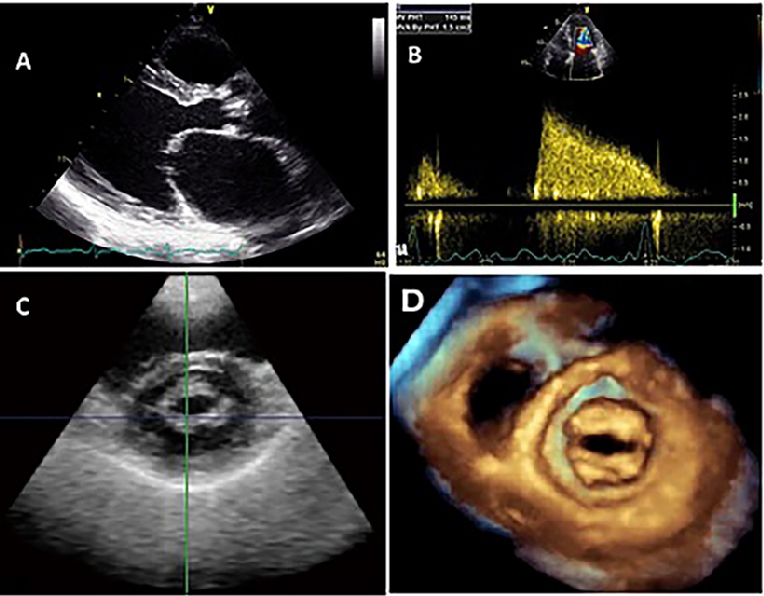

Describe the detailed anatomy of the mitral valve mv using two dimensional 2d transesophageal echocardiography tee based on the american society of echocardiographysociety of cardiovascular anesthesiology guidelines.

Mitral valve anatomy tee. The comprehensive tee examination of the mitral valve consists of a series of eight cross sectional views. Ography tee has enabled accurate noninvasive imag ing of the complex mitral valve anatomy in real time and from unique orientations previously available only to surgeons. You can now confidently identify 5 components of the mitral valve apparatus.

The standard modalities of real time 3d tee have recently been described 32. Anatomy of mitral valve mitral valve apparatus mitral valve annulus. Perturbations of the normal anatomic relations can result in mitral valve dysfunction table 3.

Assessment of mitral valve anatomy by real time 3 dimensional 3d transesophageal echocardiography tee has proven to be superior compared to 2 dimensional tee 121. The mv comprises two leaflets annular attachment at the atrioventricular junction tendinous chords and the papillary muscles pms. Surgeons skill and experience 2.